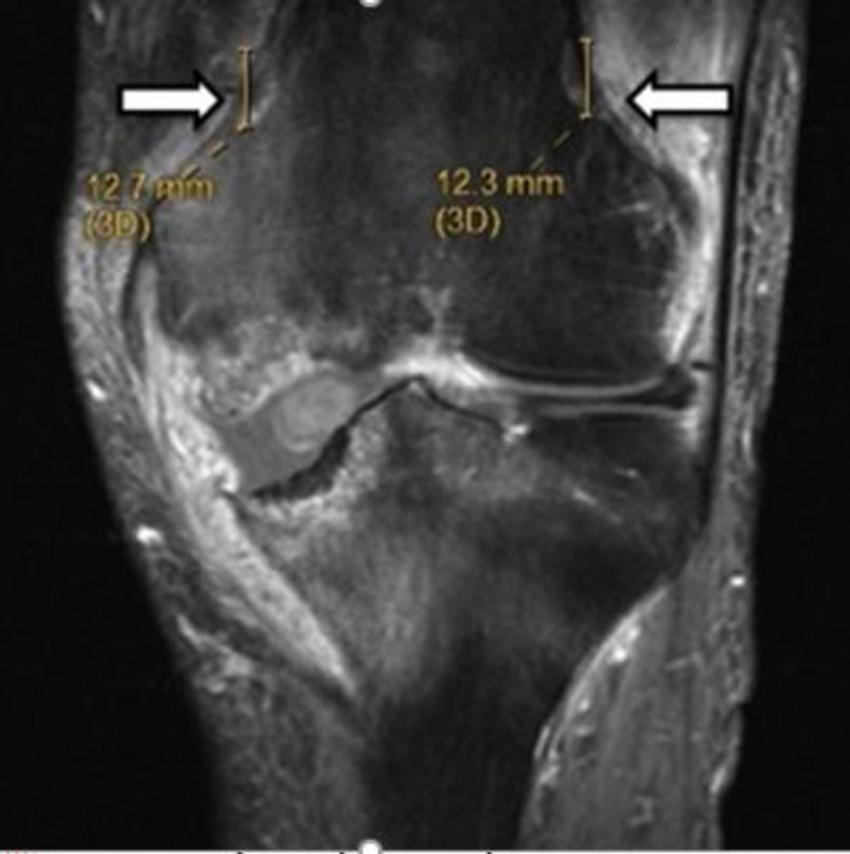

Figure 3. Image shows lesion produced by cooled radiofrequency neurotomy for chronic osteoarthritis knee pain.

High-res (TIF) version

Figure 4. Image shows lesion produced by cooled radiofrequency neurotomy for chronic osteoarthritis knee pain.